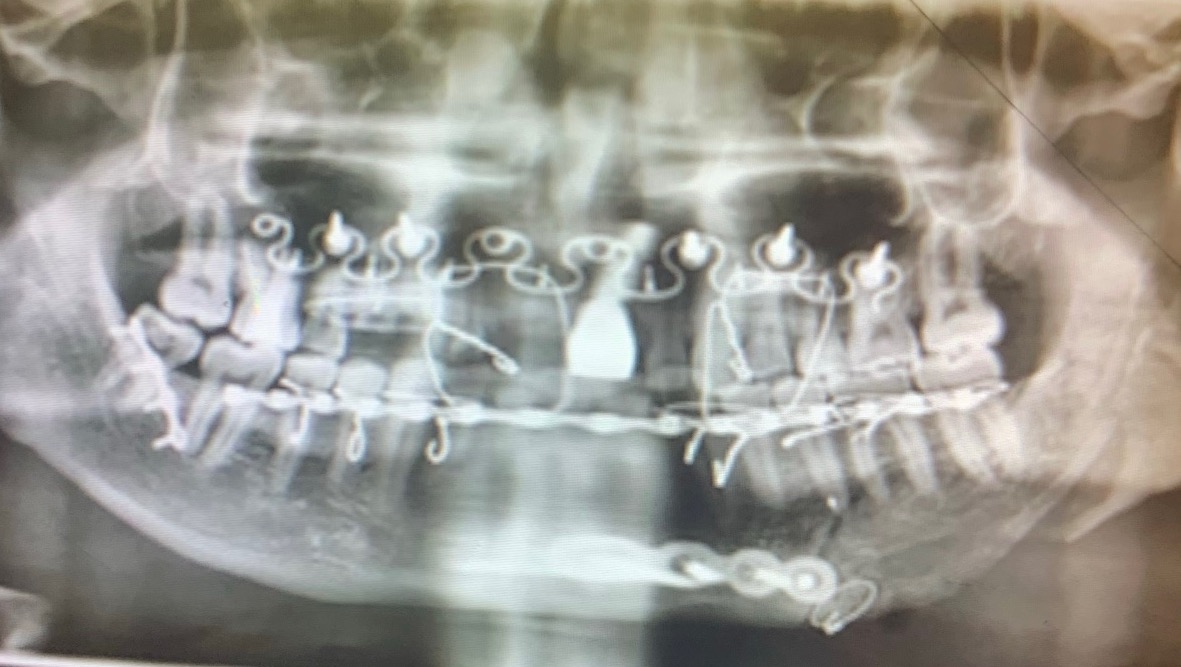

Early in the morning of June 12th, my sister received a call from Pennsylvania State Police that my little brother Jeffrey was found on the side of a dirt road near our cabin in Confluence, Pa. His throat had been slit open and there was severe damage to his face and massive blood loss. We were unsure if he was going to survive. Because of the severe trauma to his face, unfortunately he has no memory of what happened. He suffered a 4 inch laceration to the neck, 2 broken orbital bones, a broken nose, multiple jaw fractures, is missing 9 teeth, and dozens of other less severe injuries.

The state police have since closed the investigation and state that he “fell”. Because we have no answers and thanks to the police has been ruled a fall instead of attempted murder, dental insurance will not cover the cost of the teeth replacement.